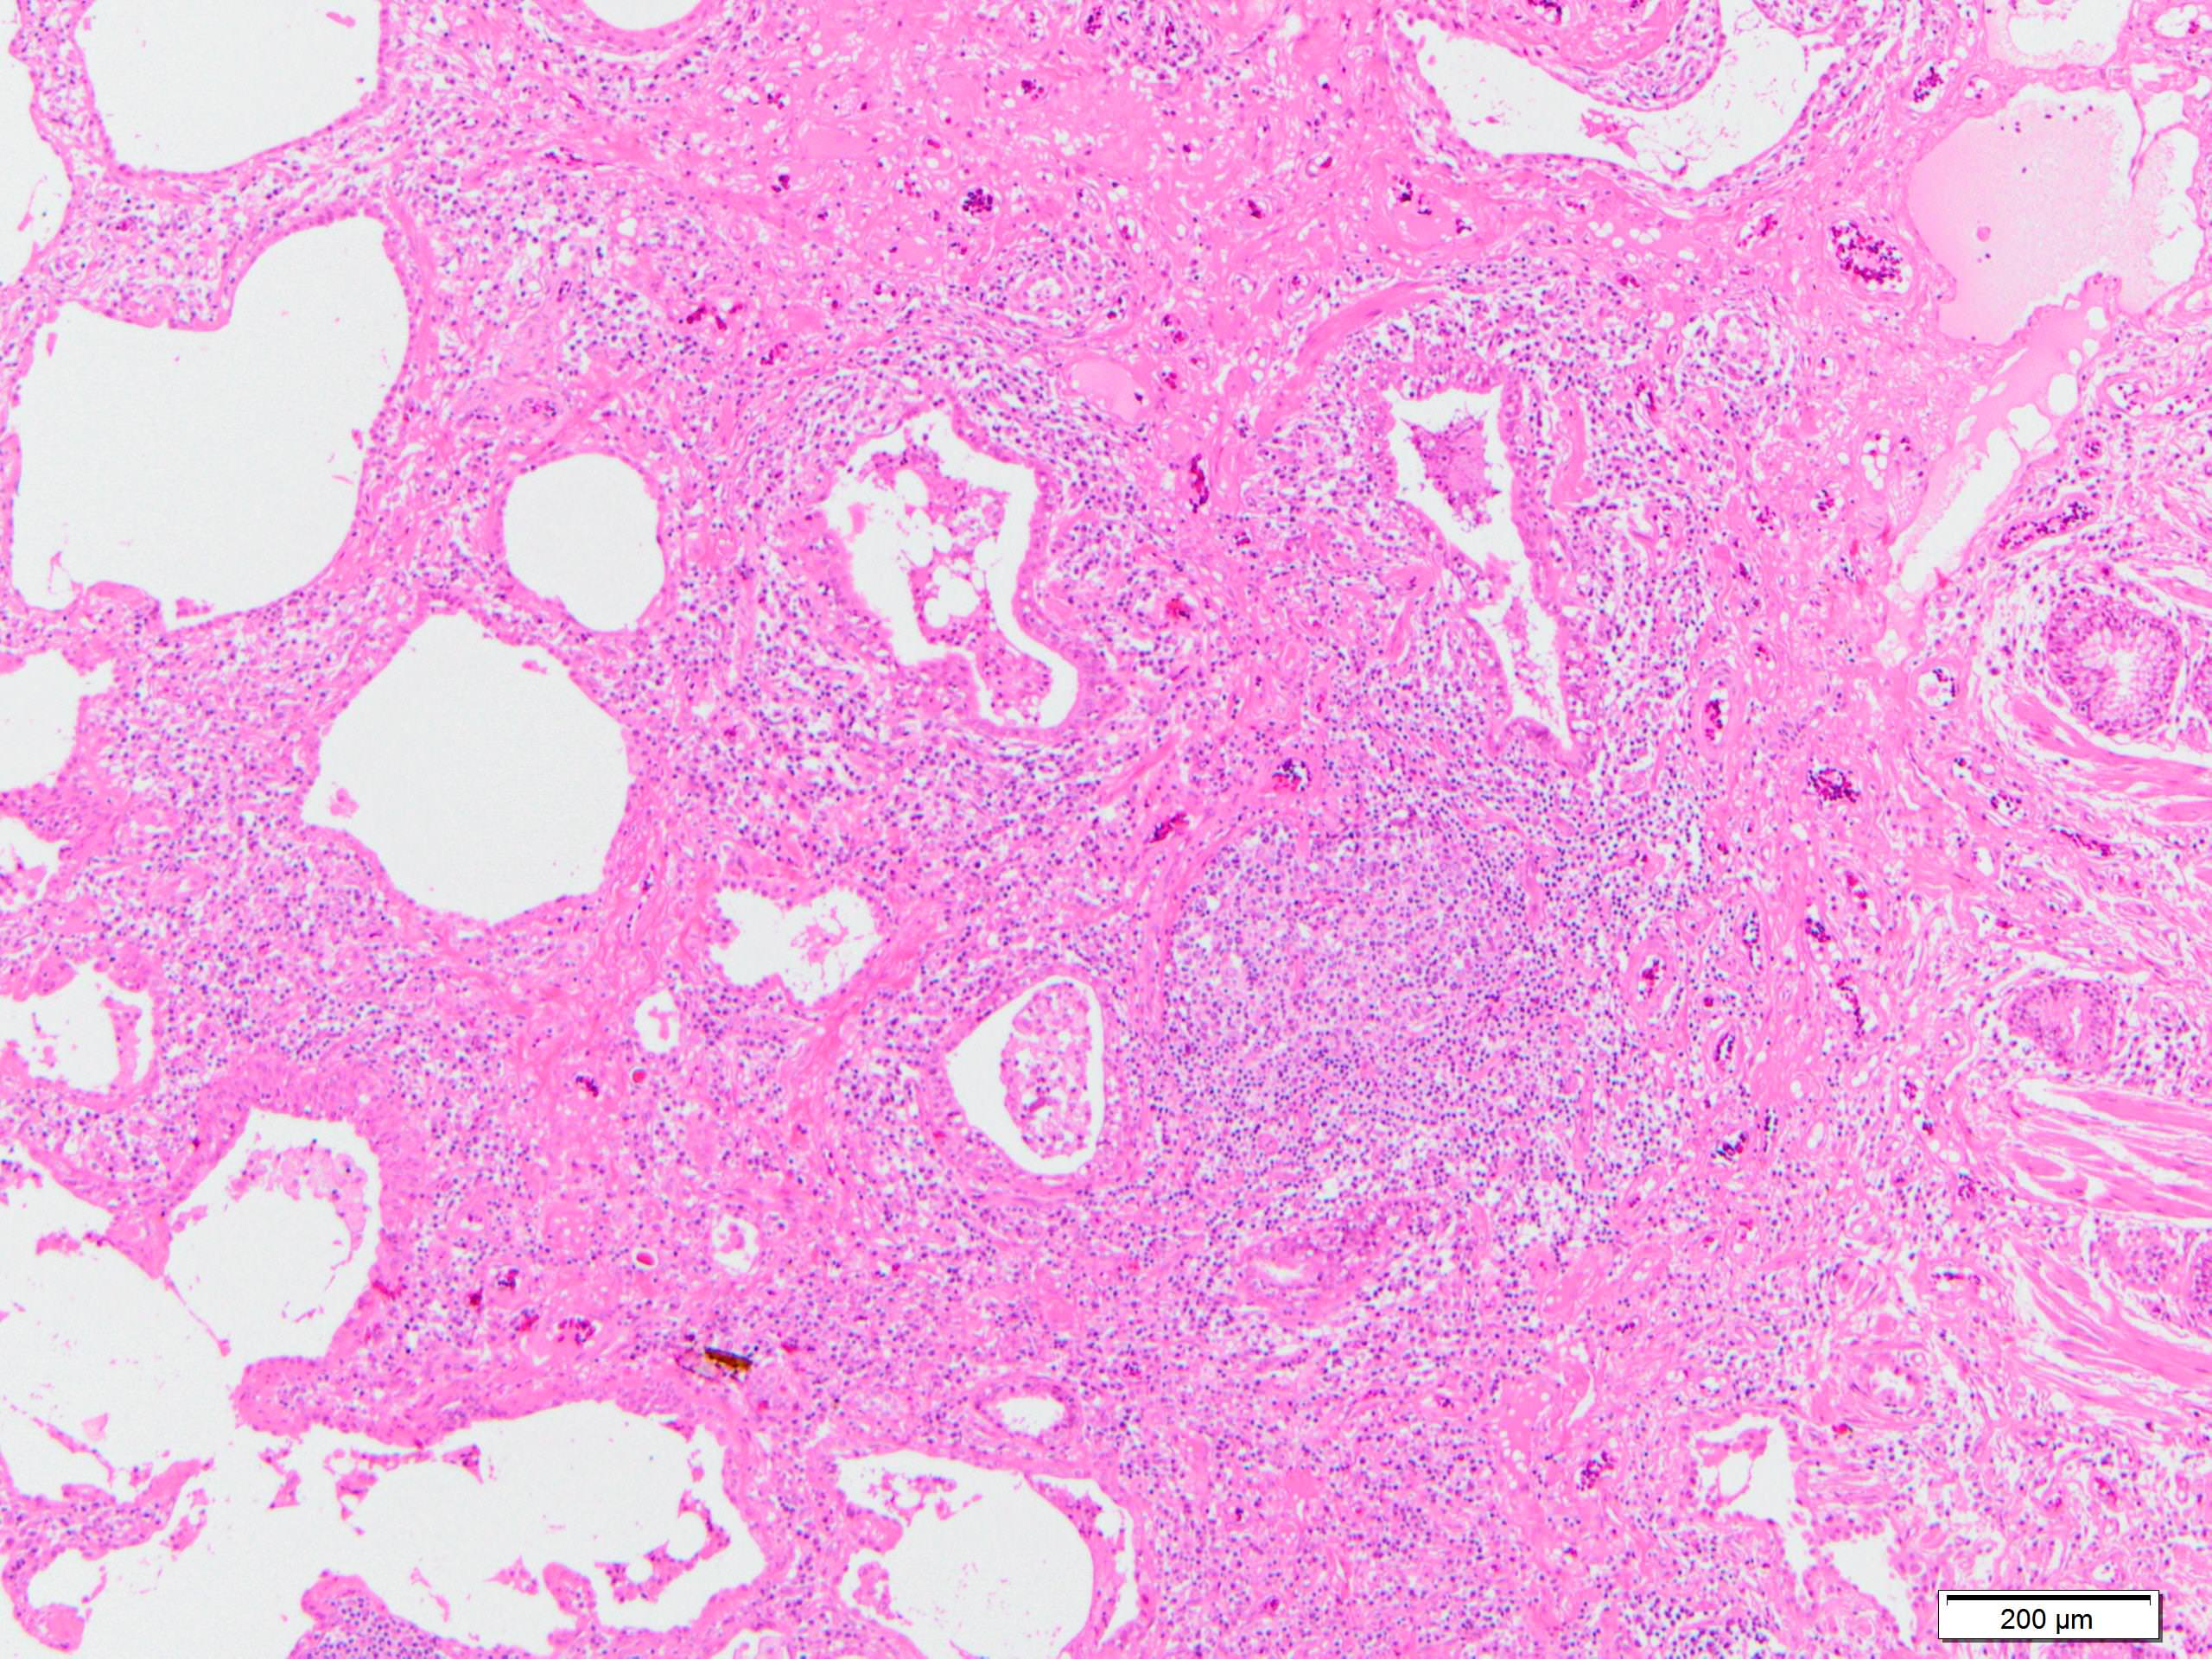

Microscopic (histologic) description

- Since there are few specific findings for NSIP pattern, it is essential to exclude other lung diseases on histology (Am J Respir Crit Care Med 2008;177:1338)

- Characteristic findings of NSIP pattern

- Diffuse and uniform inflammation ("temporal homogeneity") on low power of alveolar wall, bronchovascular bundles and pleura

- Cellular or fibrotic change

- Lymphocytic or plasmacytic infiltration

- Loose fibrosis

- Features of interstitial pneumonia with autoimmune features (IPAF) (Chest 2010;138:251):

- Lymphoid aggregates with germinal center

- Extensive pleuritis

- Prominent plasmacytic infiltration

- Dense perivascular collagen

- It is quite rare to see pure NSIP on histology - typically there are focal findings of other interstitial lung disease (Histopathology 2014;65:549)

Microscopic (histologic) images

Contributed by Akira Yoshikawa, M.D.

Differential diagnosis

- Interstitial pneumonia with autoimmune features (IPAF): lymphoid aggregates with germinal center, extensive pleuritis, prominent plasmacytic infiltration, dense perivascular collagen